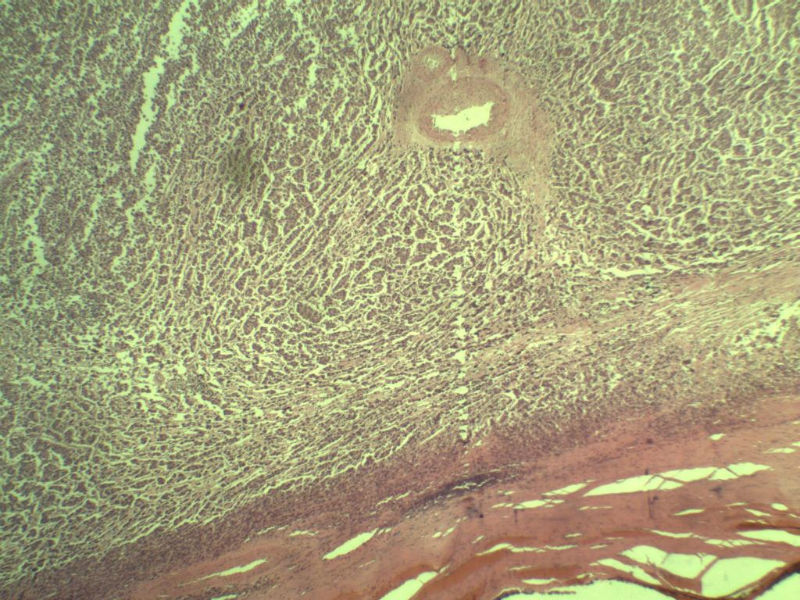

男 27岁 腹腔隐睾 5*3*2 cm, 切面灰红灰黄、实性、质中,请各位老师看看,是精原细胞瘤吗?感觉不像.腹腔隐睾图1

精原细胞瘤

典型的精原细胞瘤,隐睾易恶变